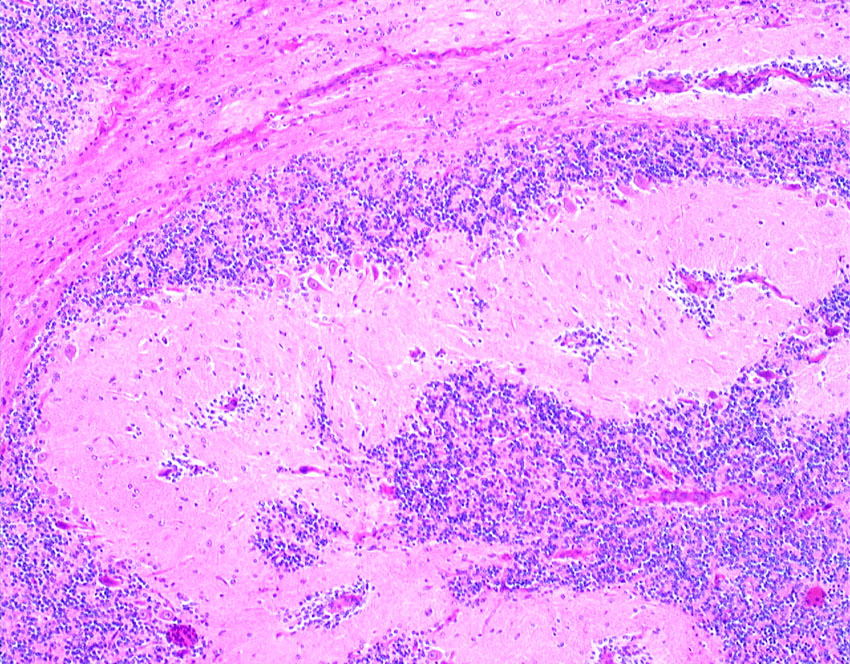

左上にはcartilage,右上にはkeratin squamous tissueがみられます。左下は繊維生組織のみdense collagenous tissueです。

生検術で胎児性癌と未熟奇形腫の混合型と診断されたために,化学療法と61.1グレイの放射線治療がなされていました。しかし,大きな松果体腫瘍が残り全摘出したものです。この子の腫瘍は治っていて元気に暮らせています。

奇形腫の照射後はいつもそうなのですが,dense collagenous tissueとfibroblastic spindle cellが組織の主体となっています。要するに肉芽腫のようなものです,ですから,手術摘出ではものすごく硬い線維性の腫瘍となっていてハサミでも切れずに難渋します。出血もしないし脳とは剥離できるのできます。放射線化学療法前の生検による組織像(悪性要素)は消失して単なる成熟奇形腫との病理診断となってしまいます。しかし,この組織のどこかに悪性度の高い細胞が潜んでいて,播種再発するなどということも経験しました。放射線治療後の病理組織診断はその後の予後の予想のためには役に立ちません。